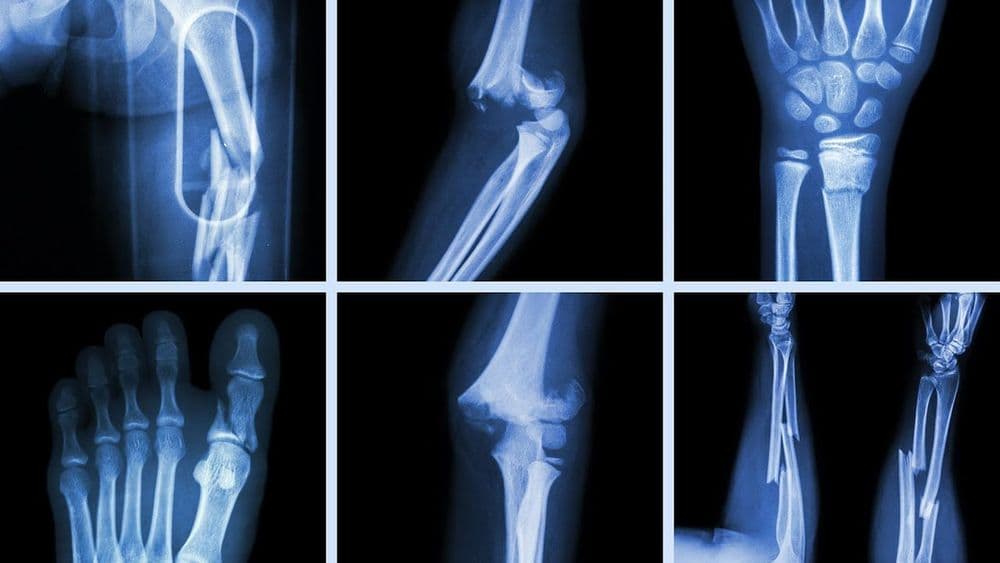

फ्रॅक्चरचे बरेच प्रकार आहेत, पण त्यामध्ये ओपन फ्रॅक्चर आणि क्लोज्ड फ्रॅक्चर हे दोन प्रकार मुख्य आहेत. जेव्हा हाड मोडते परंतु त्वचेवर कुठेही जखमेची खूण नसते तेव्हा त्याला क्लोज्ड फ्रॅक्चर म्हणतात. ज्यावेळी हाड मोडून त्वचेतून बाहेर येते त्यावेळी त्याला ओपन फ्रॅक्चर म्हणतात. ओपन फ्रॅक्चरमध्ये हाडांमध्ये खोलवर जंतुसंसर्ग होण्याचा धोका असतो. हाडे मोडून मोडून त्यांचे लहान लहान तुकडे होणे, हाडांवर विशिष्ट कोनात छेद दिला जाणे, हाडे कमकुवत झाल्यामुळे फ्रॅक्चर होणे, तसेच हेअरलाईन क्रॅक असे फ्रॅक्चरचे अनेक प्रकार आढळून येतात. फ्रॅक्चर कोणत्या ठिकाणी आणि प्रकारचे आहे यानुसार ते किती गंभीर आहे ते ठरते. जर फ्रॅक्चर गंभीर असेल तर त्यावर त्वरित योग्य उपचार करावे लागतात. नाहीतर गुंतागुंत अजून वाढू शकते. यामुळे रक्तवाहिन्या, चेतातंतू यांना इजा पोहोचण्याचा धोका असतो. तसेच हाडांमध्ये व आजूबाजूच्या टिश्यूजमध्ये जंतुसंसर्ग होऊ शकतो. फ्रॅक्चर झाल्यानंतर बरे होण्यासाठी लागणारा काळ हा रुग्णाचे वय, त्याची एकंदर शारीरिक स्थिती, आणि फ्रॅक्चरचा प्रकार यांच्यावर अवलंबून असतो. हा काळ काही आठवड्यांपासून काही महिन्यांपर्यंत असू शकतो.

डॉक्टर बहुधा फ्रॅक्चर आहे की नाही हे जखमेची तपासणी करून आणि एक्स-रेच्या मदतीने सांगतात. पण कधीकधी एक्स-रेमध्ये फ्रॅक्चर असल्याचे दिसत नाही. यात मुख्यतः काही प्रकारचे मनगटाचे फ्रॅक्चर, खुब्याचे फ्रॅक्चर, आणि स्ट्रेस फ्रॅक्चर्स यांचा समावेश होतो. अशावेळी फ्रॅक्चरचे निदान करण्यासाठी डॉक्टर सिटी स्कॅन, एमआरआय किंवा बोन स्कॅन या तपासण्या करायला सांगतात.